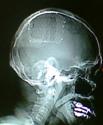

4).颅骨修补术 DR片 三维重建